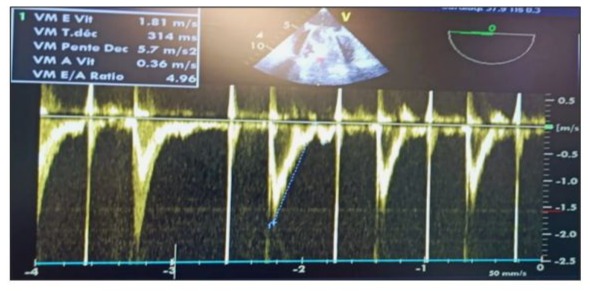

We present the clinical case of a 22-year-old female patient who underwent surgery for mitral stenosis complicated by atrial fibrillation and pulmonary hypertension. She received a mechanical valve and tricuspid valve repair. A year later, she experienced worsening symptoms. Examination revealed a thrombus on the mechanical valve. She was managed in the cardiac intensive care unit and received aspirin and heparin. Post-treatment, there was improvement in the transvalvular gradient and partial regression of the thrombus. She was discharged on acenocoumarin with regular monitoring. However, after one year (2 years post-surgery), she arrived at the emergency room with a more severe episode of acute global congestive heart failure. Upon clinical examination, crackles were detected in the lungs, along with mild hypoxia (O2 saturation 93%), and absence of fever or lower limb swelling. Blood pressure measured at 90/60 mmHg, with tachycardic atrial fibrillation (120 bpm) and a respiratory rate of 30/min. Chest X-ray revealed cardiomegaly and bilateral pulmonary edema. (Figure 1) Blood tests showed leukocytosis, elevated NT-proBNP levels (800), and moderate metabolic acidosis. Echocardiography documented near-complete blockage of the mechanical mitral valve leaflets with high transvalvular gradient and significant regurgitation. After initial stabilization with norepinephrine, heparin, diuretics, and dual antiplatelet therapy, her condition deteriorated on the fifth day with shock, hypoxia, and confusion, raising concerns about possible systemic embolisms, including secondary cerebral embolism, which was ruled out by a brain CT scan. (Figure 2) In a situation of mitral valve blood clot causing cardiogenic shock, norepinephrine dosage was increased to 15 mcg/kg/min and dobutamine started at 5 mcg/kg/min. TransThoracic Echocardiography (TTE)showed severe pulmonary hypertension, distended left atrium, high transvalvular gradient, severe mitral regurgitation, and hyperkinetic Left Ventricle (LV). Epinephrine was given, dobutamine stopped, and patient moved to operating room with equipment for perfusion and transfusion, and received vitamin K, exacyl, Vancomycin, and heating blanket.

General anesthesia induced: 250 µg fentanyl, 0.3 mg/kg etomidate, and 1.2 mg/kg rocuronium. Anesthesia maintained with sevoflurane (MAC = 1.0). Analgesia maintained: 250 µg fentanyl boluses every 30–40 min; blood gas analysis 10 min after intubation. TEE probe inserted using video laryngoscope. Patient stable with low-dose vasoactive support before cardiopulmonary bypass. Doppler ultrasound in Scarpa triangle to study femoral vein and artery, found to be patent but small in size, especially femoral artery (8 mm). TEE performed pre-sternotomy to define anesthesia and surgical strategy, evaluate lesions, and address hemodynamic instability before CPB. Bicaval view used to monitor venous cannula progression. (video 1) Upon opening Scarpa triangle, common femoral artery was smaller than available venous cannulae. Central cannulation was decided upon, with TEE monitoring throughout. LV appeared small with limited opening of one valve leaflet and complete blockage of the other. Mitral valve apparatus identified with thrombi. Anterior and inferior walls of LV retained kinetics. Oblique plane revealed LV inflow chamber and outflow tract. Right ventricle was dilated with normal aortic ring. Leaking annuloplasty seen in right atrium. Left atrium, tricuspid valve, and right ventricle were thrombus-free. In mid-esophageal view, St. Jude mechanical valve had thickened ring with thrombi on both sides. (Figure 3) Pulsed Doppler TEE at the mechanical mitral valve in the mid-esophageal view, at a perpendicular plane of 60 degrees, showing a holosystolic retrograde mitral flow velocity of 1.3 m/s. (video 2) Slight probe rotation revealed left atrium dilation, thickened leaflets, limited leaflet movement at heart crux, and blockage at atrium-ventricle junction. Hyper-echoic thrombi in left ventricle were partly obscured. (Figure 3b) TEE in 2D mode, transducer at 45° counter clockwise rotation, shows dilated left atrium with obstructed mechanical valve due to multiple thrombi at leaflets, ring, and core. Leaflet opening beneath appendage is absent and limited on opposite side. Ring appears thickened with fibrinous thrombus. Reverberation echoes obscure left ventricle walls except for anterior and inferior walls with preserved kinetic activity (Video 3).

Figure 2:Contrast brain CT scan in axial slices, performed to investigate delayed thromboembolic complications, returned without abnormalities.

Figure 14: Postoperative pulsed Doppler TEE after weaning from CPB on the mechanical mitral valve showing an antegrade mitral flow velocity of the E wave at 2 m/s (>1.5 m/s) and an E/A ratio of 4.96, indicating elevated filling pressures in the absence of an A wave due to atrial fibrillation.